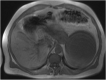

Isolated splenic cystic echinococcosis is a rare condition. In Greece the number of cases has declined substantially in the last 20 years. The spleen is the second most common extrahepatic site of cystic echinococcosis. Albendazole is safe, but mebendazole can be used as a substitute, in case of adverse reaction. Our patient was diagnosed with isolated splenic echinococcal cyst, during the investigation for newly diagnosed type 2 diabetes mellitus. We opted for elective splenectomy, based on a risk assessment due to the patient's working conditions, and treatment with albendazole represented a safety measure until surgery was possible. The patient developed acute hepatocellular injury to albendazole after eight weeks of treatment. This was confirmed through rechallenge with albendazole after discontinuation of the drug. Postsplenectomy the treatment with mebendazole proved to be safe with no adverse reactions. Even though, albendazole is known to be safe, monitoring of hepatic enzymes and full blood count should be offered. In case of toxicities, mebendazole with or without praziquantel can be used. Toxicity to mebendazole can be similar to albendazole but a trial is worthwhile. In our patient, treatment with mebendazole was uneventful.